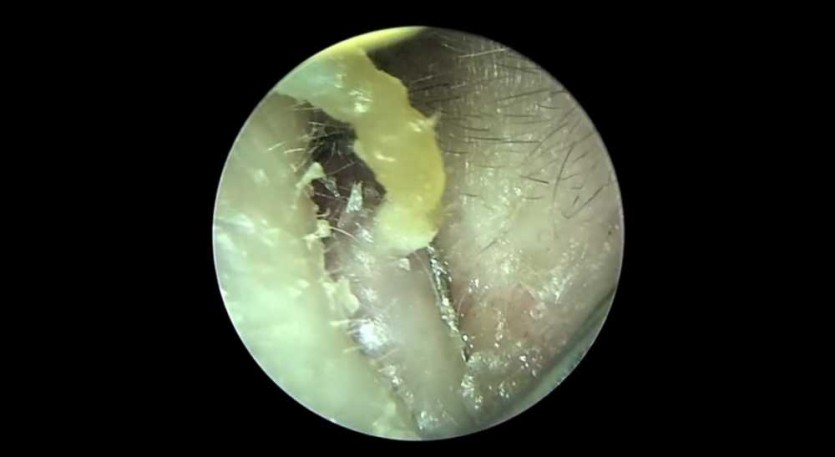

극혐) 귀 입구 왕건이 피지제거 작성자 정보 이단아이유 작성 849 조회 작성일 2025.09.21 04:35 컨텐츠 정보 본문 관련자료 이전 아니 근데 오늘 며칠이냐? 작성일 2025.09.21 06:12 다음 부엌서 관등성명이 절실히 필요한 사람 댓글 (1 ) 작성일 2025.09.21 03:03 댓글 0 등록된 댓글이 없습니다. 로그인한 회원만 댓글 등록이 가능합니다.